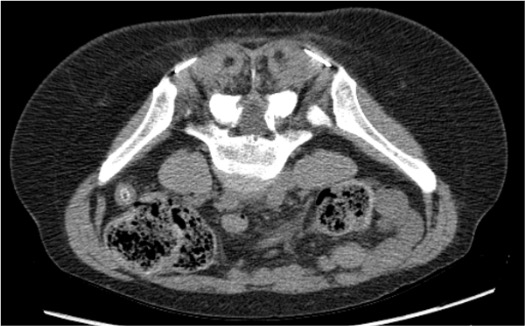

Lateral Femoral Cutaneous Nerve (LFCN)

- Arises from L2–L3 nerve roots; purely sensory nerve

- Exits pelvis under inguinal ligament medial to ASIS; runs superficial to tensor fascia lata into the thigh

- Target: 1 cm medial and 1 cm inferior to ASIS — where nerve exits into thigh between fascia layers

- Approach: CT or US; supine or prone; 22G needle

- Syndrome: meralgia paresthetica — lateral thigh burning/numbness

| Nerve | CT Target | Best CT Plane | Key Anatomy |

|---|---|---|---|

| LFCN | Medial-inferior to ASIS; deep to inguinal ligament | Axial | Between fascia iliaca and tensor fascia lata |